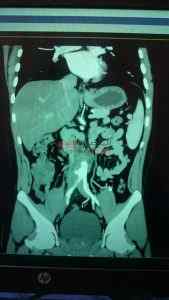

تمكن فريق جراحى بقسم فريق جراحه الأوعية الدمويه برئاسة الدكتور مسعد سليمان ، بإجراء أول حاله تمدد بشريان الأورطي باستخدام القسطرة التداخلية بجامعة المنصورة .

يضم الفريق الدكتور تامر عبد الحي ، الدكتور محمد فرج ، الدكتور محمد شكري ، الدكتور أحمد مسعد ، الدكتور نشأت محمد ، وأشار الدكتور مسعد مريض تعافي بعد القسطره وتم الاطمئنان عليه وينتظر خروجه في خلال ٤٨ ساعة ، مشيرا أن حالة التمدد بشريان الأورطى بسبب ضعف جزء من جدار هذا الشريان بالبطن مما يؤدي إلى التمدد وخطورة الانفجار بسبب ضغط الدم المتواجد بداخله ، ومعظم تمدد الأوعية الدموية يحدث في ذلك الجزء من الشريان الأورطي الذي يمر في البطن ويسمى تمدد الشريان الأورطي البطني ، إذا كان التمدد كبيراً جدا يمكن أن يسبب آلاماً مبرحة وتورماً في البطن يكبر تدريجياً وإذا انفجر فقد يسبب نزيفاً داخلياً شديداً غالبا ما يكون مميتاً إلا عندما يتم إنقاذ الموقف بعملية جراحية سريعة.